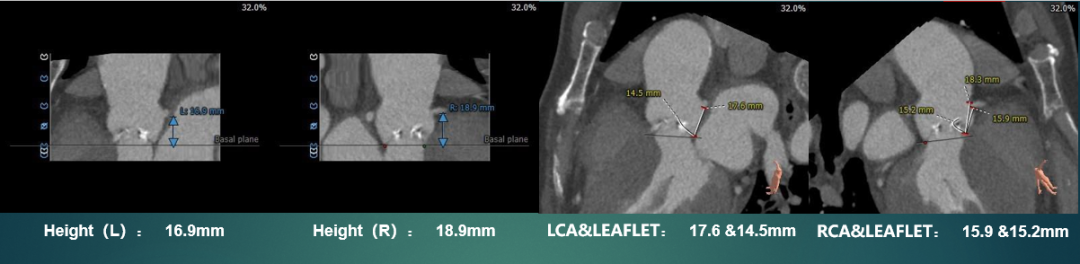

主动脉根部测量

CT特点:Type 0型二叶式主动脉瓣,左右冠不同窦,瓣叶中度钙化伴增厚,钙化分布相对均匀,主要分布于瓣叶边缘及其附着缘,瓦氏窦及窦管交界内径可,升主动脉内径扩张,最大径约43.6mm,左右冠脉开口高度可,无冗长瓣叶;非横位心,心室壁肥厚,心腔偏小,降主动脉及双侧髂总动脉分叉处可见多发钙化斑块。

瓣上测量

瓣上测量:瓣叶中度钙化,钙化分布相对均匀,钙化主要分布在瓣叶边缘及瓣叶附着缘,锚定力量主要来源于瓣上6-10mm。